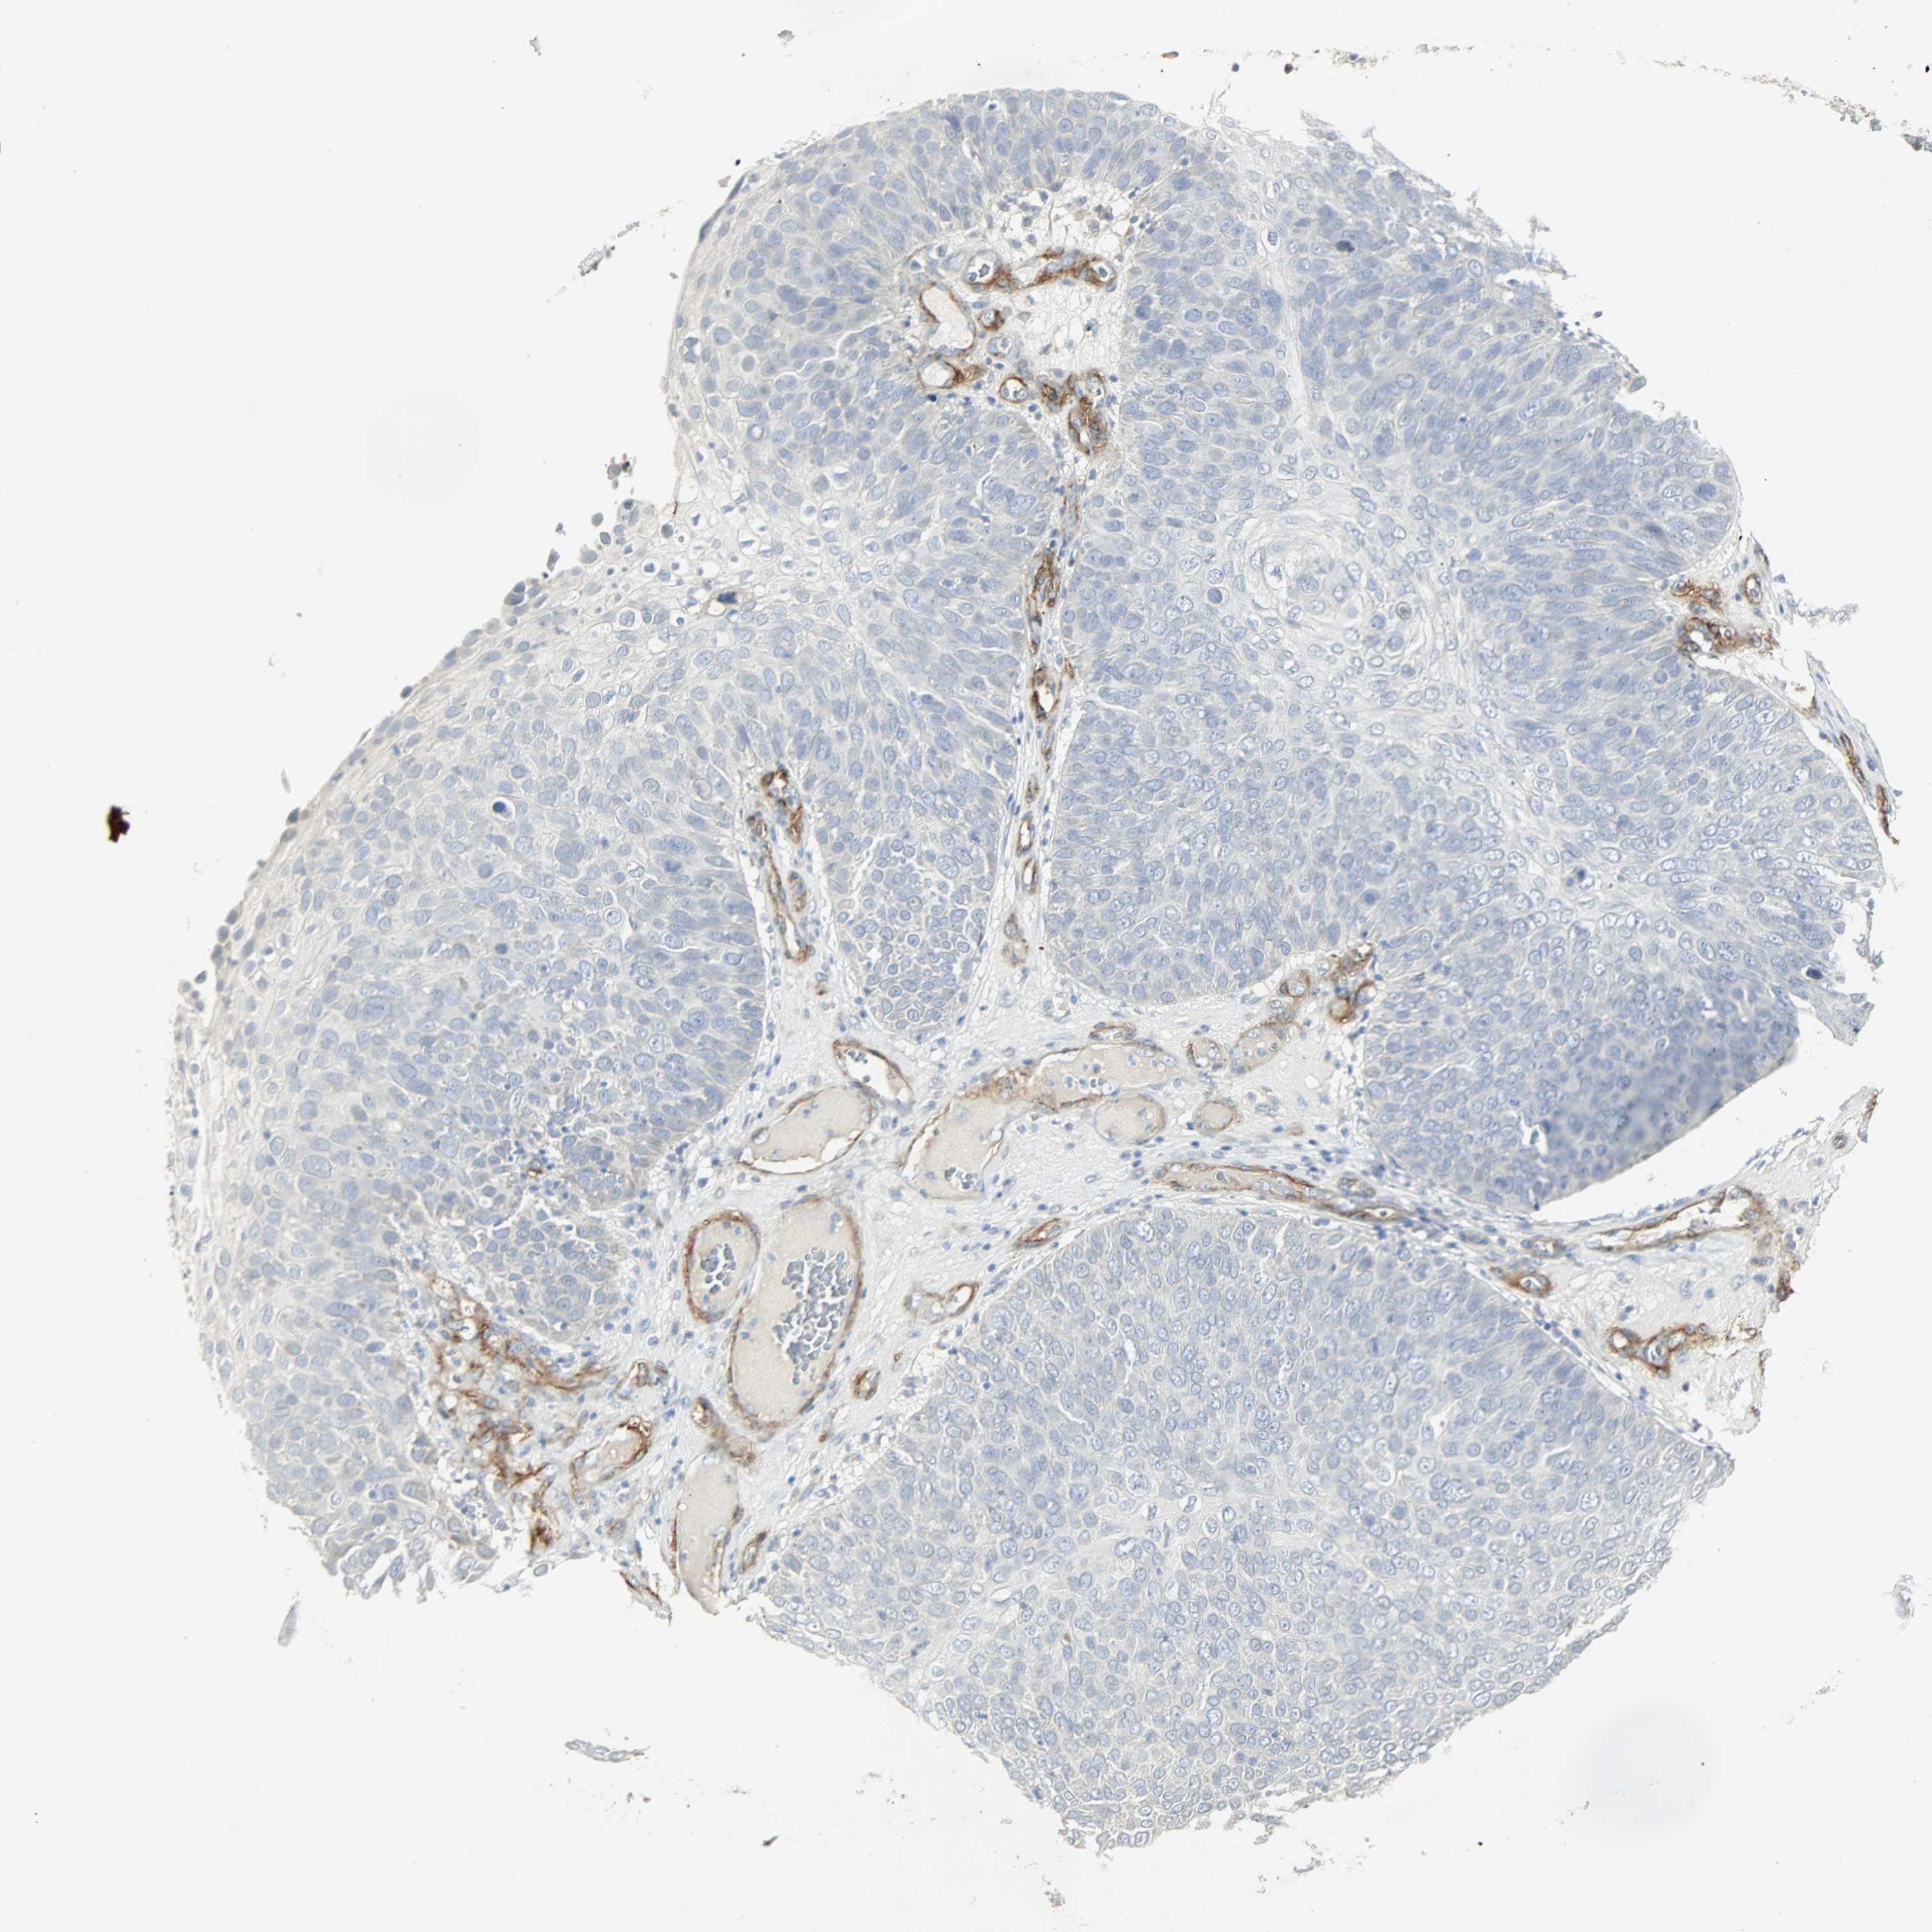

SKIN CANCER - Protein expressioni

A mouse-over function shows sample information and annotation data. Click on an image to view it in a full screen mode. Samples can be filtered based on level of antibody staining by selecting one or several of the following categories: high, medium, low and not detected. The assay and annotation is described here.

Each image is clickable and will lead to virtual microscopy that enables deeper exploration of all samples and also displays staining intensity scores, fraction scores and subcellular localization as well as patient and tissue information for each sample.

Antibody HPA005128

Squamous cell carcinoma, NOS

Basal cell carcinoma